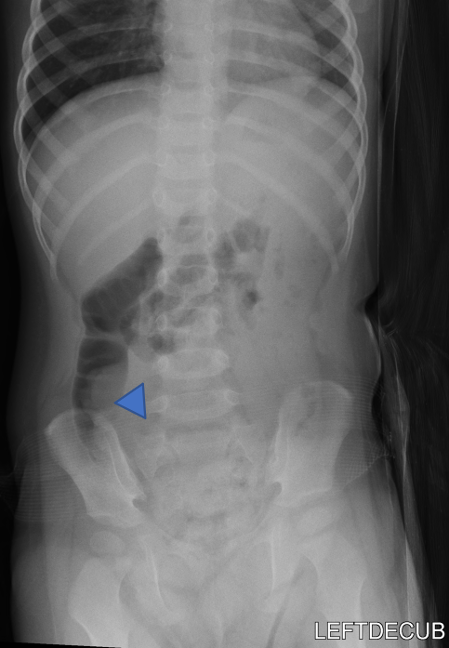

(Figure 3)

Figure 3: Supine and left decubitus abdomen radiographs.

- There is paucity of gas in the ascending colon (arrow).

- The ascending colon is partially air-filled on the left decubitus view, with a soft tissue density in the cecum (arrowhead). This soft tissue density is delineated by air, resembles the crescent sign. No evidence of peritoneal free air.